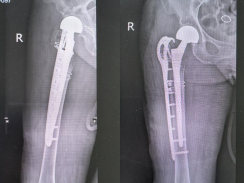

患者术前 X 线片 患者术后X线片

在多学科专家的紧密协作下,手术团队顺利为患者完成手术。术后,骨科三病区护士长杨洁带领护理团队实施精细化护理,高磊副主任医师、拓一帆主治医师、周鑫住院医师共同负责精准治疗与病情管理,患者恢复平稳,各项指标持续好转,最终康复出院。此次成功救治,充分彰显了医院在复杂髋关节翻修领域的技术实力与多学科协同作战的综合能力。